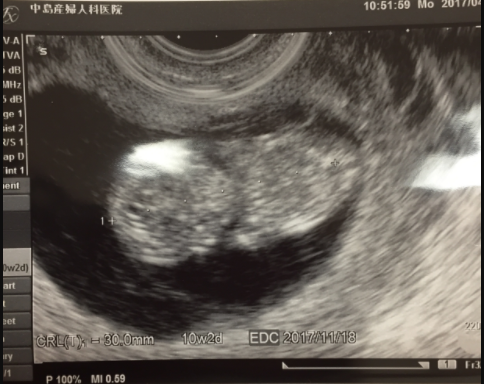

10週5日(10w5d・男の子)|かむい さん(22歳)

エコー写真撮影時のエピソード:

初めての妊娠だったんでお腹の中に赤ちゃんがいるのが信じられなかったですね。まだお腹も大きくなかったですし。 妊娠から2回目の検査でした。 小さくても人らしい形をしていてお腹の中にいる写真を見た時ほんとにいるだと実感できました。